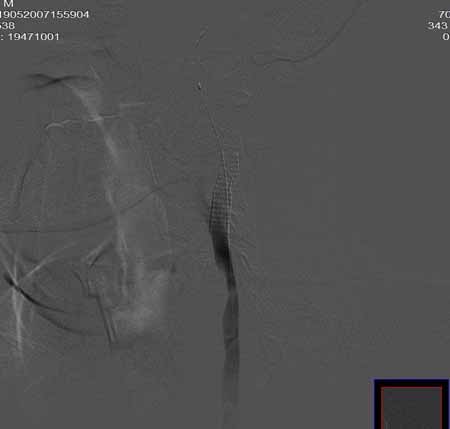

男,60岁。

腹主动脉、颈总动脉、颈内动脉狭窄支架置入术,最少放了三个支架吧,得十几万吧。

颈总动脉支架置入术。

指针宽了些

wallstent9*50可以全部覆盖,可以节约些

当然楼住的选择无可指责